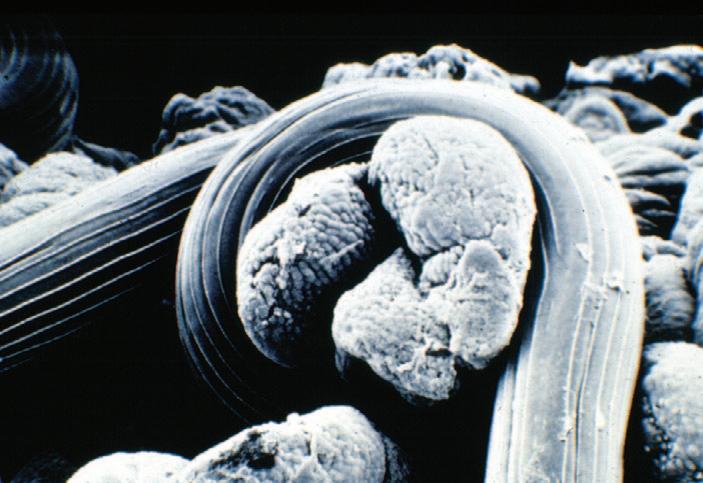

Heavy infections with Nematodirus larvae damage the small intestine, leading to diarrhoea and dehydration. The adult worms coil around villi in the small intestine (Figure 2) to maintain their location within the gut, causing damage. Some of the most severe clinical signs are caused by the immature parasites as they migrate through the gut. In some cases this can lead to sudden death before the parasites have matured to the egg laying stages. This means that heavily infected lambs can die before eggs are seen in a faecal egg count (FEC).